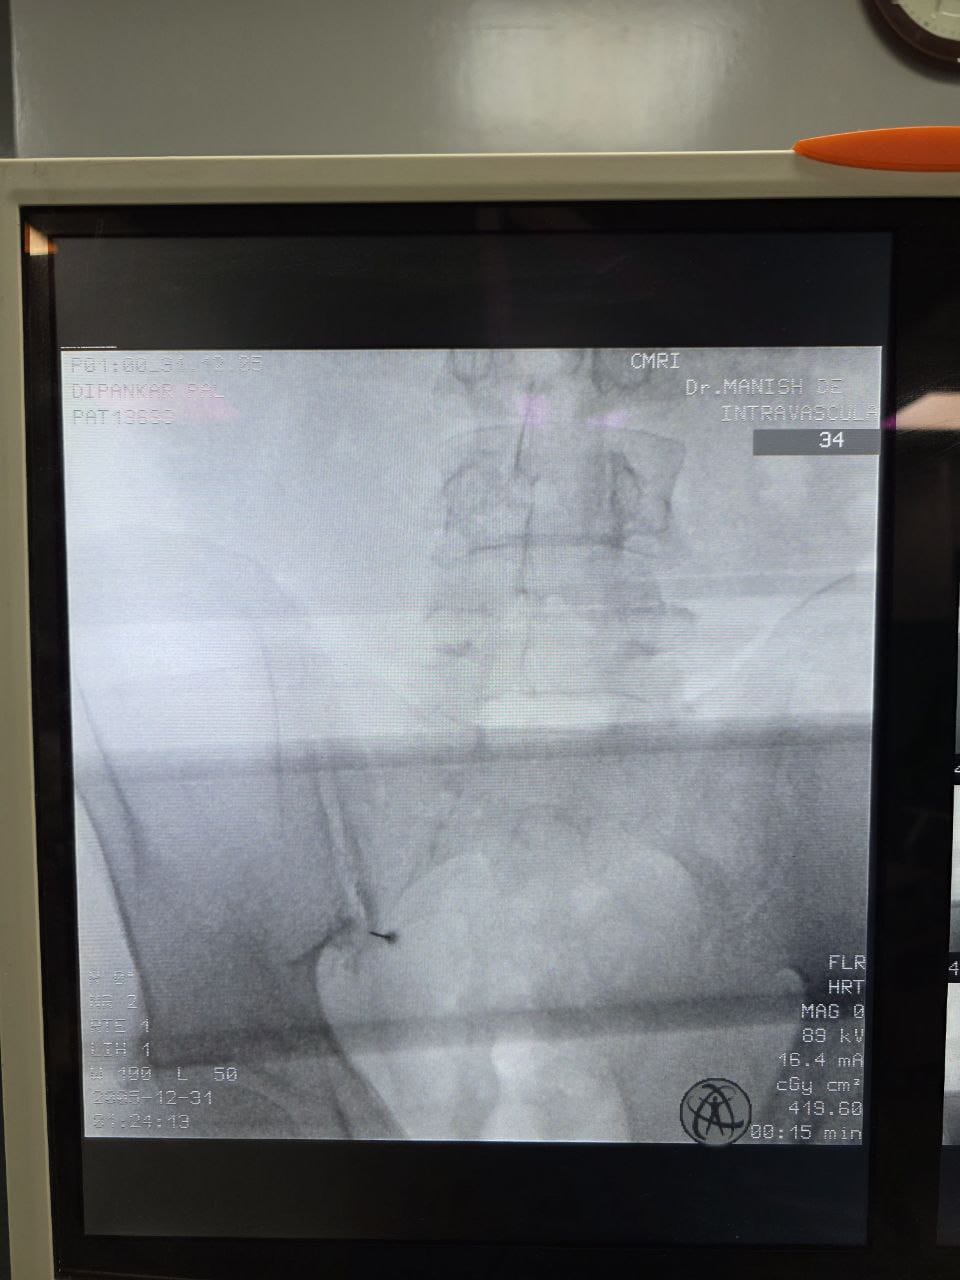

Struggling with chronic pain? Get advanced, personalised pain management from Dr. Manish De, one of Kolkata’s leading pain specialists. From knee pain, heel pain, low back pain, frozen shoulder, migraines, cancer pain to post-TKR persistent pain—Dr. De offers safe, evidence-based treatments across multiple locations: